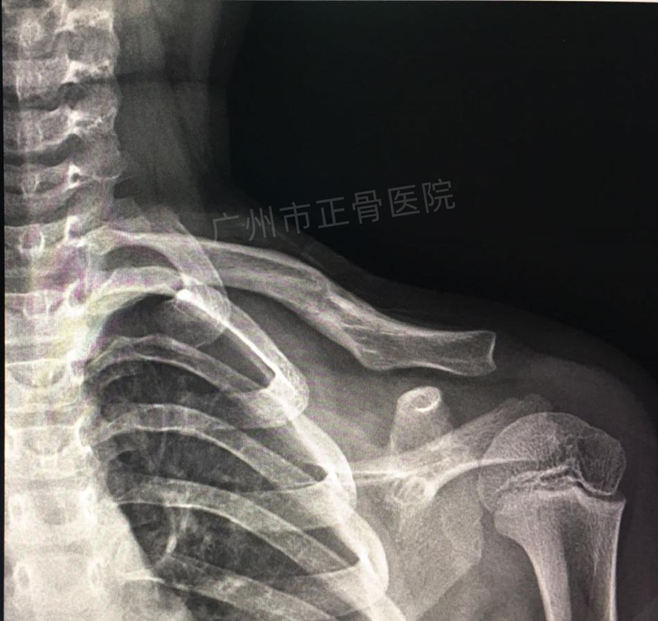

治疗:运用正骨手法复位后小夹板外固定治疗。复位后复查X线片提示骨折端对位对线明显改善。给予三角巾悬吊患肢,指导患者适当功能锻炼。4周后复查X线提示骨痂生长,骨折端稳定,予拆除夹板,检查患者肩关节活动正常。4个月后复查X线,骨性愈合。

▲4个月后,骨折线消失,骨性愈合